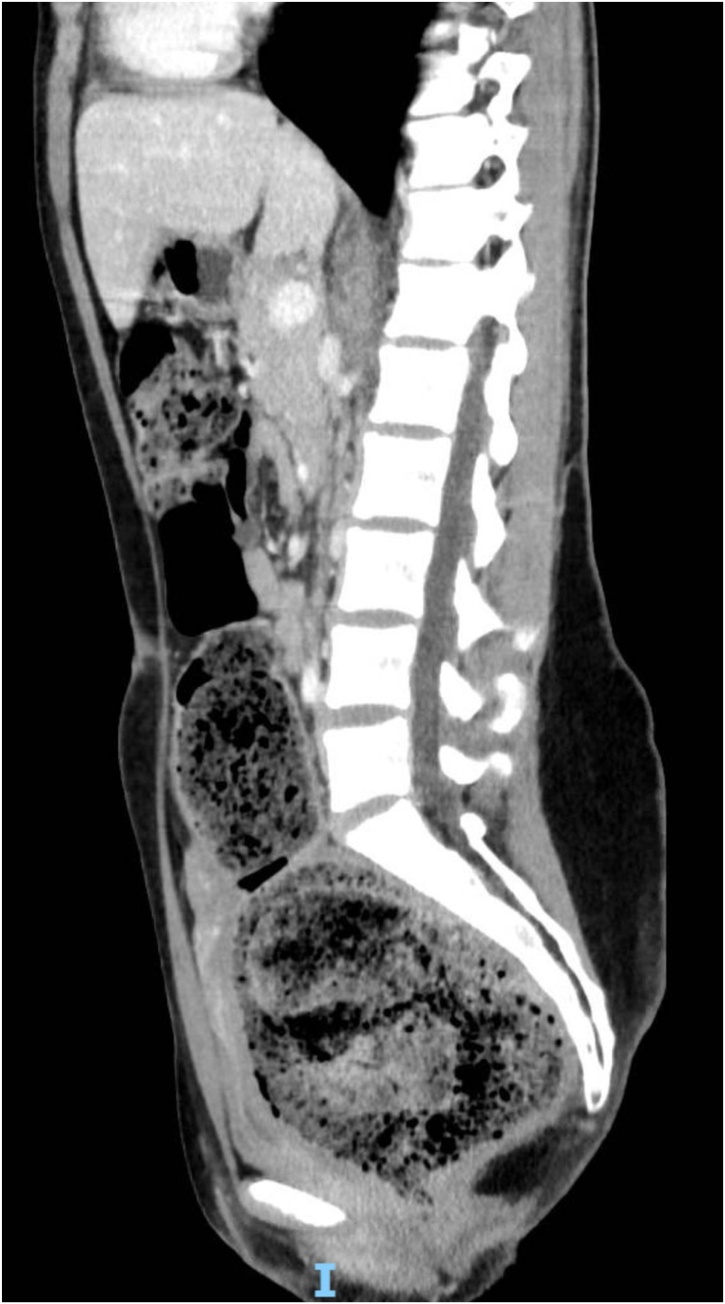

A 19-year-old Caucasian female patient was referred to General Surgery Department after her PCP found megacolon and megarectum in a computed tomography (CT) scan of the abdomen and pelvis (Fig. 1, Fig. 2, Fig. 3). Her evaluation and diagnostic procedures were performed by a board-certified general surgeon with colorectal surgery training. She had a lifelong history of intermittent abdominal pain as well as constipation requiring daily laxatives and enemas. Other than that, she did not have a history of medical or surgical problems. She did not smoke and her family history was unknown since she was raised by her aunt. Her abdominal exam was within normal limits. Her ano-rectal exam was normal on inspection, the digital rectal exam demonstrated a normal resting tone as well as hard stool in the rectal vault. The CT scan was significant for a severely distended sigmoid colon and rectum. Her lab work included a complete blood count and a comprehensive metabolic panel, these were within normal limits. Given her presentation the work up included: colonic transit study (Fig. 4), barium enema (Fig. 5) and a full thickness rectal biopsy after rectal de-impaction. Anal manometry was not performed. The colonic transit study (Sitz Marker Test) displayed most of the markers in her sigmoid colon and rectum at day number five. The Barium enema showed similar findings to those of the CT scan which included a dilated rectum starting immediately above the anorectal ring. She was taken to the operating room for a rectal biopsy. Under general anaesthesia and in lithotomy position a manual de-impaction was performed followed by rectal irrigation and a full thickness rectal biopsy. An anoscope was used to identify the level of the target area. In order to include the submucosa 2 full thickness rectal biopsies at 1.5 and 3 cm from dentate line in the posterior aspect were taken. Distal and proximal to this location a 2-0 Vicryl full thickness traction stitch was placed. This allowed total control of the tissue to ensure full thickness specimens. Both defects were closed with running 2-0 Vicryl. The patient tolerated the procedure well; she was discharged home the same day on a soft diet and had no post-operative complications. Pathology results showed the lack of ganglion cells in the submucosa (Fig. 6a-b). Routine H&E staining, as well as Immunohistochemistry stains for S100, Smooth Muscle Actin (SMA) and Calretinin were performed. Both SMA and Calretinin were negative despite appropriate controls which confirmed diagnosis of Hirschsprung’s disease (Fig. 7a-b). The patient was then referred to a tertiary care center. The chief of Pediatric Surgery took over her case. She underwent manual fecal de-impaction, a confirmatory rectal biopsy, laparoscopic seromuscular sigmoid biopsies for levelling and a diverting loop ileostomy for decompression of the dilated colon and rectum. The distal sigmoid colon biopsy showed few ganglion cells; the proximal colon had a normal amount. Seven months later she underwent an uneventful laparoscopic proctectomy with perianal colo-anal pull through procedure of which she recovered well. The operation was uneventful. Two months later her loop ileostomy was closed. She has been doing well. She is having two bowel movements a day with very good control and no longer suffers from constipation.

Fig. 2.

CT scan showing megarectum and fecaloma in a sagittal section.